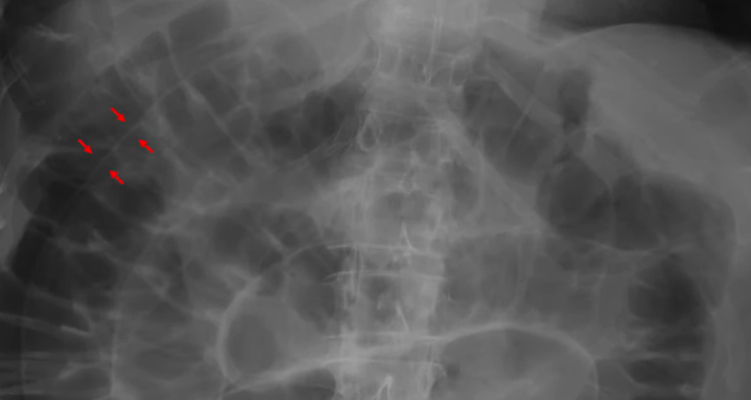

To what structure are the arrows pointing?

A) Intestinal walls